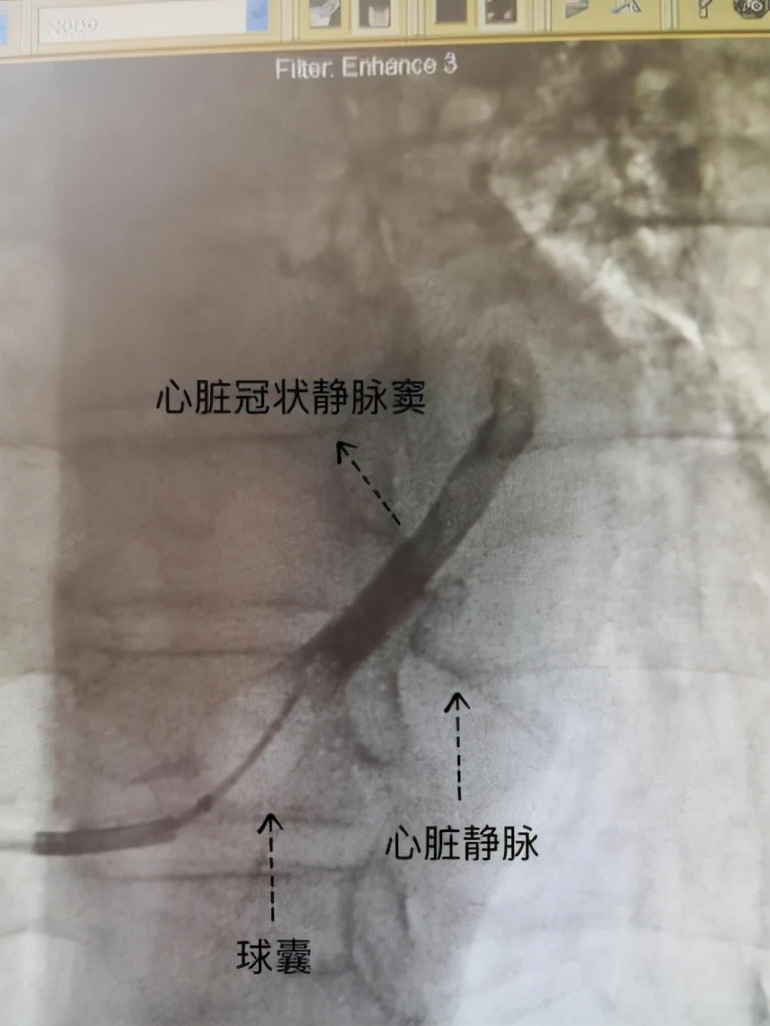

心脏冠状静脉窦逆行造影

CRT-D的手术置入技术要求很高,除需掌握常规起搏器置入技术外,还要掌握冠状静脉窦逆行造影技术和左室电极心脏静脉置入技术。同时因为该款起搏器有除颤功能,因此该款起搏器体积明显大于常规起搏器,所以术中不易术制作囊袋,以上因素都大大增加了手术难度。孟亮主任带领心血管内三科团队共同努力,成功为患者安置了CRT-D,手术顺利。术后患者双心室同步性明显改善,心功能明显恢复,乏力、呼吸困难等症状明显改善,患者夜内可平卧入睡,未再出现憋醒现象,轻体力活动不受限,生活质量大大提升,患者及家属非常满意。